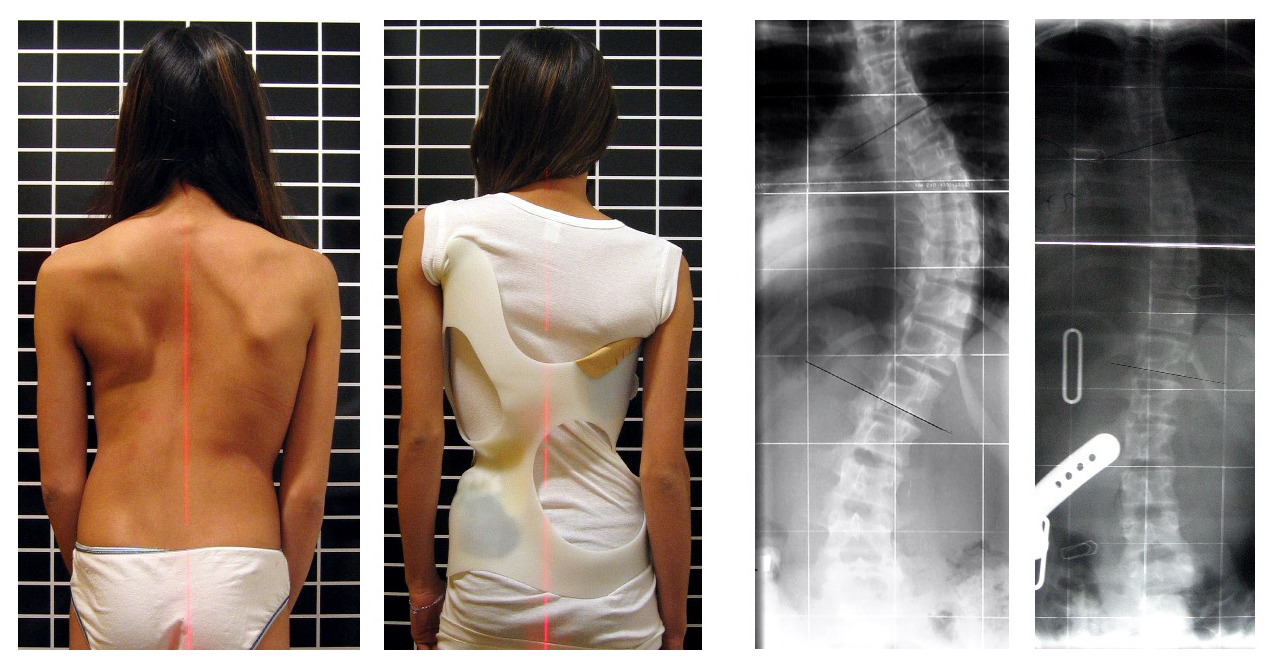

보조기 치료는 척추의 성장이 남아있는 환자에게 주로 적용되며, 만곡의 진행을 억제하는 것이 목표이다.[94] 보조기는 척추에 압력을 가하여 만곡을 교정하는 역할을 한다.[94] 뼈가 계속 성장하는 환자 중 코브 각도가 20~29°인 경우, 연령, 6개월 동안의 코브 각도 증가, 리서 징후 및 임상 증상을 고려하여 진행 위험에 따라 보조기를 착용해야 한다.[97] 코브 각도가 30° 이상인 경우에도 보조기를 착용해야 한다.[97] 그러나 이는 지침일 뿐 모든 환자에게 적용되는 것은 아니다.[97]

가장 일반적으로 사용되는 보조기는 TLSO로, 보스턴 보조기와 같은 형태를 띠며, 겨드랑이에서 엉덩이까지 덮는 코르셋과 유사한 장치로, 유리 섬유 또는 플라스틱으로 맞춤 제작된다.[94] 일반적으로 하루 22~23시간 착용하는 것이 권장되며, 척추의 만곡 부위에 압력을 가한다.[94] 보조기의 효과는 보조기 디자인과 보조기 제작 전문가의 기술뿐만 아니라 환자의 순응도 및 하루 착용 시간에 따라 달라진다.[94] 야간 전용 보조기는 아이가 잠자는 동안 밤에만 착용하며, 변형을 과도하게 교정한다.[95]

보조기가 질병의 악화를 예방한다는 증거는 있지만, 삶의 질, 외모 또는 요통을 변화시키는지 여부는 불분명하다.[98]

보조기 치료는 척추의 성장이 남아있는 환자에게 주로 적용되며, 만곡의 진행을 억제하는 것이 목표이다.[94] 보조기는 척추에 압력을 가하여 만곡을 교정하는 역할을 한다.[94] 뼈가 계속 성장하는 환자 중 코브 각도가 20~29°인 경우, 연령, 6개월 동안의 코브 각도 증가, 리서 징후 및 임상 증상을 고려하여 진행 위험에 따라 보조기를 착용해야 한다.[97] 코브 각도가 30° 이상인 경우에도 보조기를 착용해야 한다.[97] 그러나 이는 지침일 뿐 모든 환자에게 적용되는 것은 아니다.[97]가장 일반적으로 사용되는 보조기는 TLSO로, 보스턴 보조기와 같은 형태를 띠며, 겨드랑이에서 엉덩이까지 덮는 코르셋과 유사한 장치로, 유리 섬유 또는 플라스틱으로 맞춤 제작된다.[94] 일반적으로 하루 22~23시간 착용하는 것이 권장되며, 척추의 만곡 부위에 압력을 가한다.[94] 보조기의 효과는 보조기 디자인과 보조기 제작 전문가의 기술뿐만 아니라 환자의 순응도 및 하루 착용 시간에 따라 달라진다.[94] 야간 전용 보조기는 아이가 잠자는 동안 밤에만 착용하며, 변형을 과도하게 교정한다.[95]

보조기가 질병의 악화를 예방한다는 증거는 있지만, 삶의 질, 외모 또는 요통을 변화시키는지 여부는 불분명하다.[98] 한편, 수영은 물속의 부력이 중력과 대항하여 척추에 가해지는 부담을 줄여주기 때문에 척추측만증 교정 및 재활에 큰 효과를 볼 수 있는 운동으로 알려져 있다.[149]